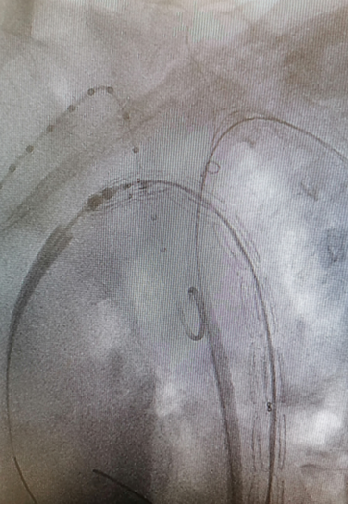

★Case 4 主动脉夹层+ARSA

治疗难点:弓上分支变异,迷走右锁骨下动脉+Kommerell憩室,夹层破口位于ARSA根部,累及LSA

手术策略:单分支支架,分支重建迷走右锁骨下动脉+续接覆膜支架

结果:假腔完全隔绝,弓上分支通畅